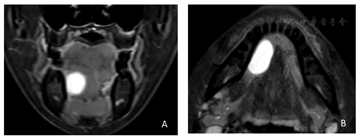

影像学检查:颌面部MRI平扫示右口底椭圆形异常信号,边界清楚,信号均匀,范围约为2.3 cm×1.1 cm,T1W1低信号,T2W1高信号。DWI未见弥散受限,舌下腺囊肿可能(图2)。

穿刺抽出蛋清样黏液,呈拉丝状。颌面部MRI平扫右口底见椭圆形异常信号,边界清楚,信号均匀,范围约为2.3 cm×1.1 cm,T1W1低信号,T2W1高信号。DWI未见弥散受限。结合病史、临床检查及影像学检查,最终诊断为右舌下腺囊肿。